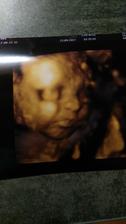

24.5. 2017 kontrolní ultrazvuk. Jsi krásný medvídek a srdíčko tluče překrásně

12.6.2017 Screening v 1 trimestru. JSI KRÁSNÁ ZDRAVÁ HOLČIČKA!!! TP podle MS i UZ 18.12.2017